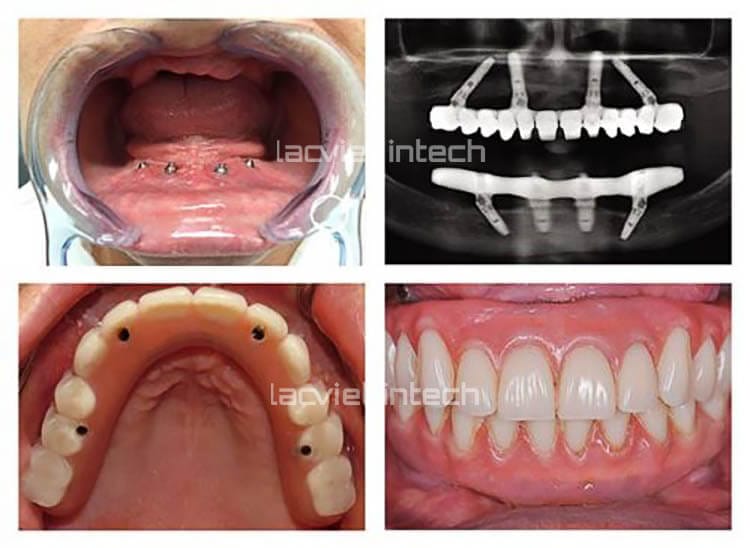

All-on-Four thay thế toàn bộ răng đã mất bằng cách cấy ghép 4 trụ Implant ở mỗi hàm, tại vị trí răng cửa. Trong đó có 2 trụ đặt thẳng và 2 trụ đặt nghiêng.

- 4 trụ Implant có vai trò như những chân răng thật giúp nâng đỡ hàm giả phục hình thân răng.

- Hàm giả thân răng gồm 12 răng sứ/ nhựa được gắn cố định trên thanh bar Titanium CAD/CAM.